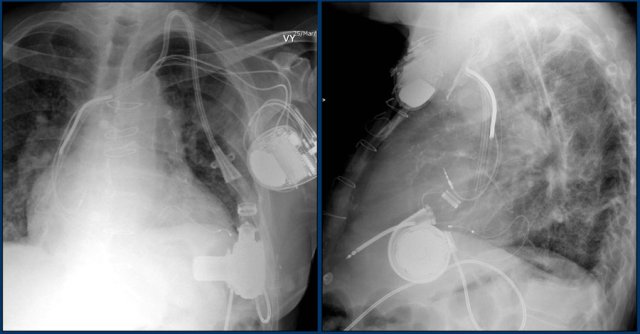

Left ventricular assist device

A left ventricular assist device (LVAD) is a surgically implanted device that takes over ventricular pump function in patients with severely impaired ejection fraction.

They were initially implanted as a bridge to cardiac transplant or during myocardial recovery, but are now also used in patients not suitable for transplant.

Here we see a patient with a LVAD.

The outflow cannula is inserted in the apex and the radiolucent outflow cannula is connected to the ascending aorta.

Also note the triple lead, double shock coil ICD and previous LIMA graft clips.